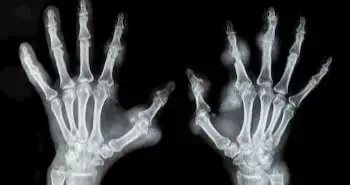

Adalimumab is a tumour necrosis factor (TNF) inhibitor involved to treat various types of arthritis states like ankylosing spondylitis and rheumatoid arthritis. It is the top-selling medication with $18 billion in sales in 2017 alone globally. The following license cessation of Adalimumab has glimpsed the emergence of the variously related biosimilar. The current study assessed the Adalimumab related biosimilars evidence in the treatment of rheumatoid arthritis (RA) from bio-originator trials to present context for critical review with relation to related biosimilars.

At present, three Adalimumab biosimilars are present which are the EMA (European Medicines Agency) and/or FDA (US Food and Drugs Administration) approved. The Samsung Bioepis’s SB5, Amgen’s ABP 501 and Boehringer Ingelheim’s (BI0 695501 are the three biosimilars. These all biosimilars meet up with their pre-specified equality criteria. The noticed references and biosimilar products exhibited subtle variations with regards to clinical responses and adverse events. The induction of these biosimilars will provide excellent opportunities to enhance treatment options for RA and other related issues. However, to certify safety and efficacy, a real-world data assessment of these biosimilars is required.